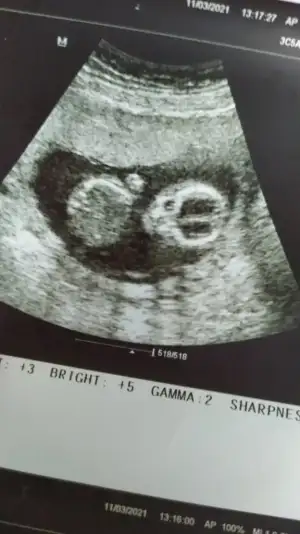

Bacak arasini acmadi ama nubdan belki anlayanlar bi yorum yapabilir bekliyorum kizlar 🤭😍

Eklentiler

• IMG-20210311-WA0013.webp

IMG-20210311-WA0013.webp

27,1 KB · Görüntüleme: 40